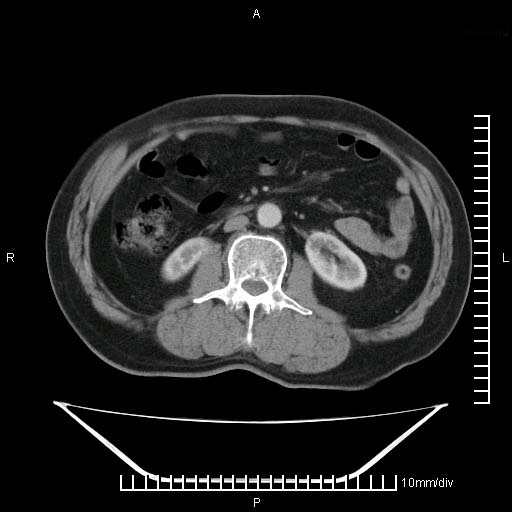

标题: CT25082:肝脏增强:男性,70岁 [打印本页]

标题: CT25082:肝脏增强:男性,70岁

患者以心脏疾病收住院,腹部无明显症状,b超查肝脏有占位。

增强效果不理想。考虑转移,胆囊壁明显增厚,不排除胆囊癌肝转移。

病灶无强化,考虑囊肿。

牛眼征,中心坏死无强化,外缘强化,最外缘又见低密度,考虑转移,与脓肿鉴别

肝内多发转移瘤,右下肺炎症并少量胸水。胃壁增厚建议胃镜,胰尾部“病变”为肠管。

1)肝脏多发性转移瘤(不排除胰尾癌转移所致可能)。2)腹水。3)右侧少量胸腔积液。

ct25082 结果:转移瘤

外院mr结果:胰尾恶性占位。